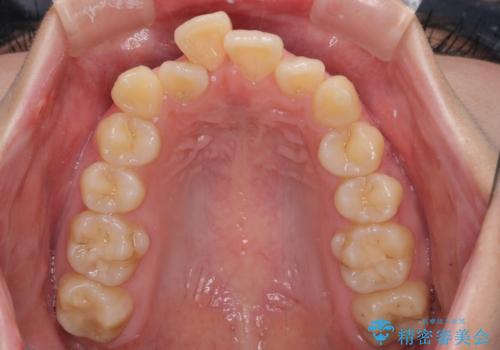

- 前歯のデコボコと突出感を気にして来院された患者様です。

上下左右第一小臼歯4本を抜歯して、積極的に口元を引っ込めるよう、ワイヤー装置にて矯正治療を行うこととしました。

口の閉じにくさが改善され、横顔のシルエットも大幅に改善されました。